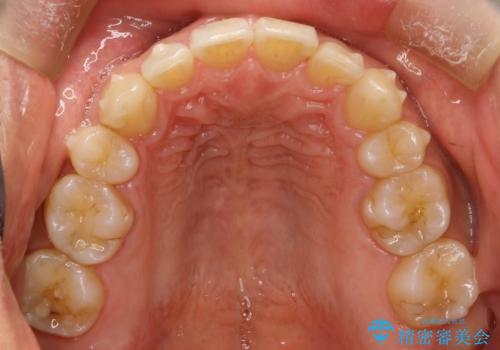

- 以前、上下左右4本抜いてワイヤー矯正をしていた方で、後戻りで下の前歯のガタガタを気にして来院されました。

マウスピース矯正にて、下の歯はIPR(歯と歯の間を削る)を入れることでガタガタの改善、咬み合わせの深さも改善をはかる治療計画をたてました。